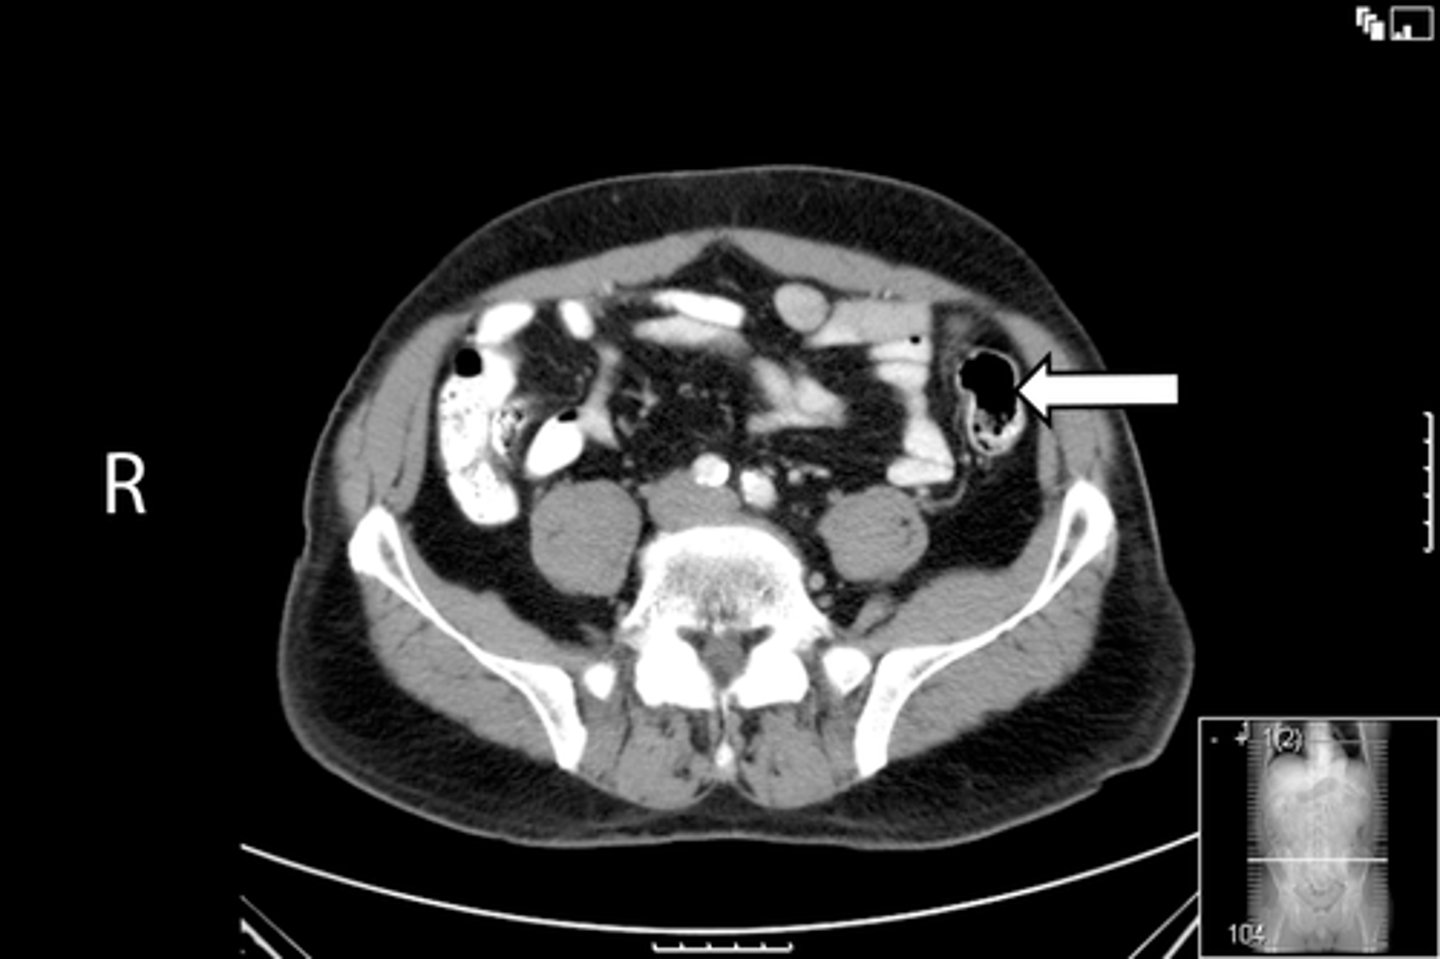

Axial bony pelvis CT

What is the image?

<p>What is the image?</p>

L ilium

What is indicated in the image?

<p>What is indicated in the image?</p>

L sacroiliac joint

R ilium

R sacroiliac joint

Sacrum